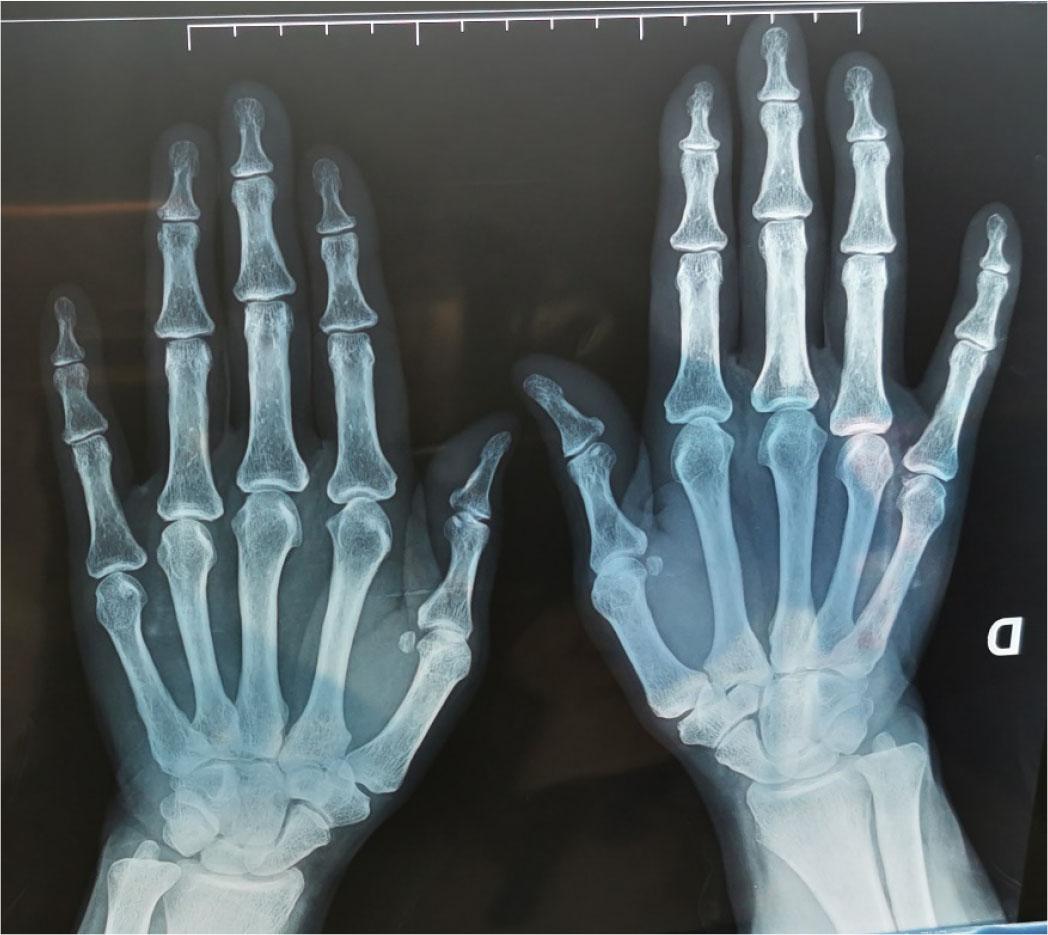

Standard X-ray of hands and wrists: absence of erosive lesions consistent with rheumatoid arthritis.